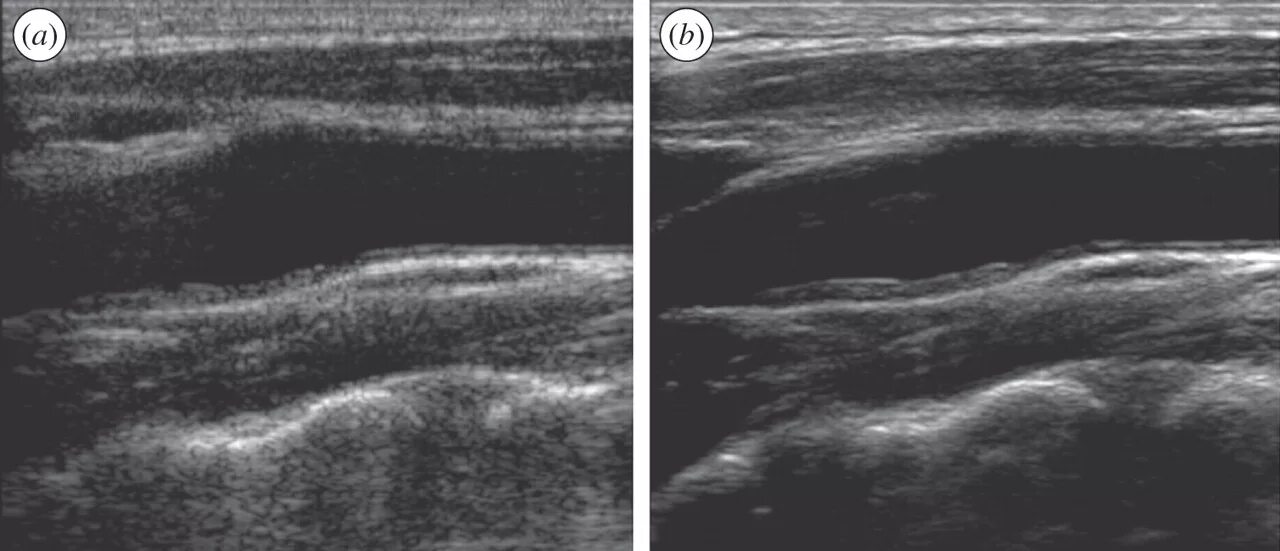

Атеросклероз на узи